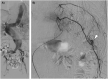

Displaced rib fractures can injure intercostal vessels leading to chest wall hematomas. As the bleeding occurs within the vessel, compression of the vessel wall helps in preventing further bleeding. Therefore, chest wall hematomas rarely result in shock. A thin 78-year-old man transferred to the emergency department with complaints of left dorsal pain due to an injury. He had a history of hypertension and aorta dissection. He arrived at the ED in a state of shock and presented with a large left dorsal wall mass. Subsequent imaging using computed tomography angiography revealed a large hyperdense hematoma at the left dorsal-flank wall along with rib fracture (11th intercostal artery). Moreover, a large fusiform aneurysm was detected from the abdominal aorta to the iliac arteries. Extravasation of the contrast agent was detected at the branch of the 11th intercostal artery, and hence, embolization was performed. The dermis, which comprises collagen and elastin fibers, plays an important role in vessel compression to prevent bleeding. The aortic media also comprises collagen and elastin fibers. Cell turnover, loss of collagen, and excessive elastolysis are associated with the formation of abdominal aortic aneurysms. The systemic degeneration of connecting tissue (collagen and elastin fiber) appears to be progress in patients with an aortic aneurysms and history of aortic dissection compared with other healthy older individuals. Physicians should be cognizant of the potential unexpected large hematoma complications if a risk of systemic connecting tissue degradation exists, as seen in patients with aortic aneurysm or aortic dissection.